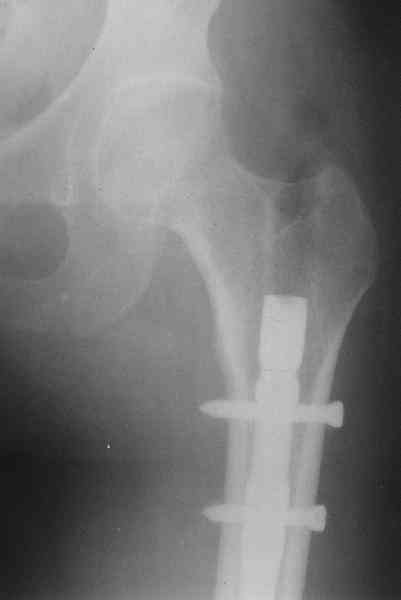

Оперирована в январе 2007 года по выходе из комы и восстановления витальных функций. Накостный остеосинтез DCP-LC. Снимки прилагаются.

Через 4 месяца стали беспокоить боли и деформациябедра. На снимке угловая деформация AP - варус 11 град.; lateral - 29 град. Объем движений в коленном суставе: ограничение сгибания до 90 град. Локально - патологическая подвижность в нижней трети бедра. Локальная гипертермия, отек мягких тканей. Гиперемии нет. Передвигалась на костылях.

В мае 2007 года оперирована в Уральском НИИТО г. Екатеринбурга. Выполнено: полузакрытое удаление пластины и винтов, IM блокируемый остеосинтез.